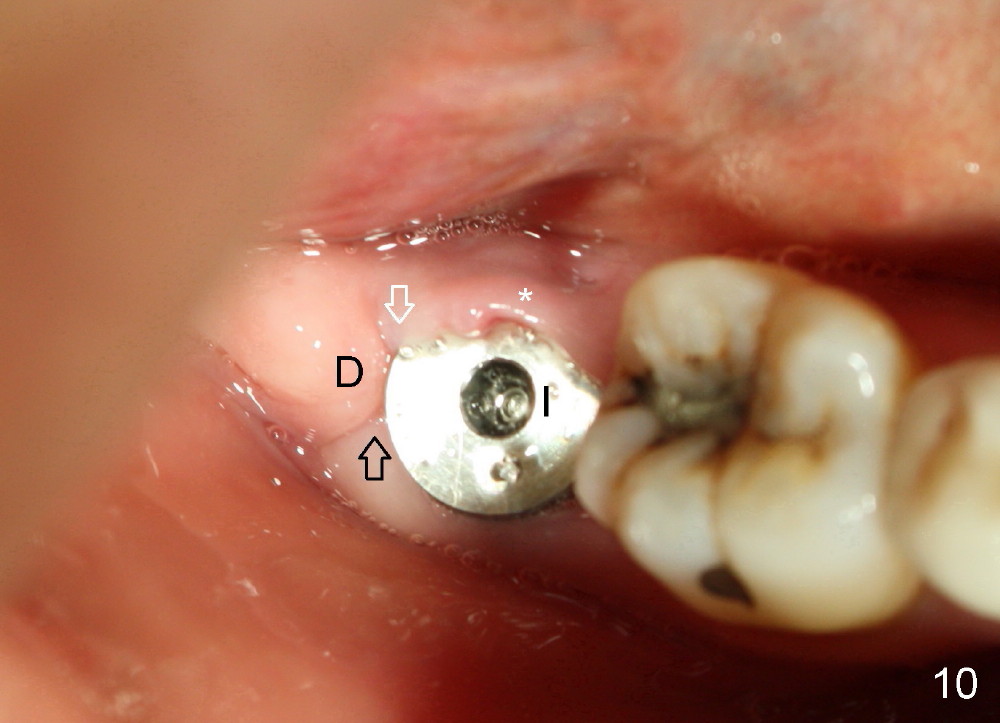

The patient returns 22 days postop (Fig.8-10). The gingiva heals around the implant. There is excess lingual gingiva (Fig.9,10 *), which should recede gradually. Fig.7 is an illustration (from Fig.4) to show how the socket is closed.. A suture is placed (black line) to approximate buccal (black arrow) and lingual (white arrow) gingiva distal to the implant (blue circle).